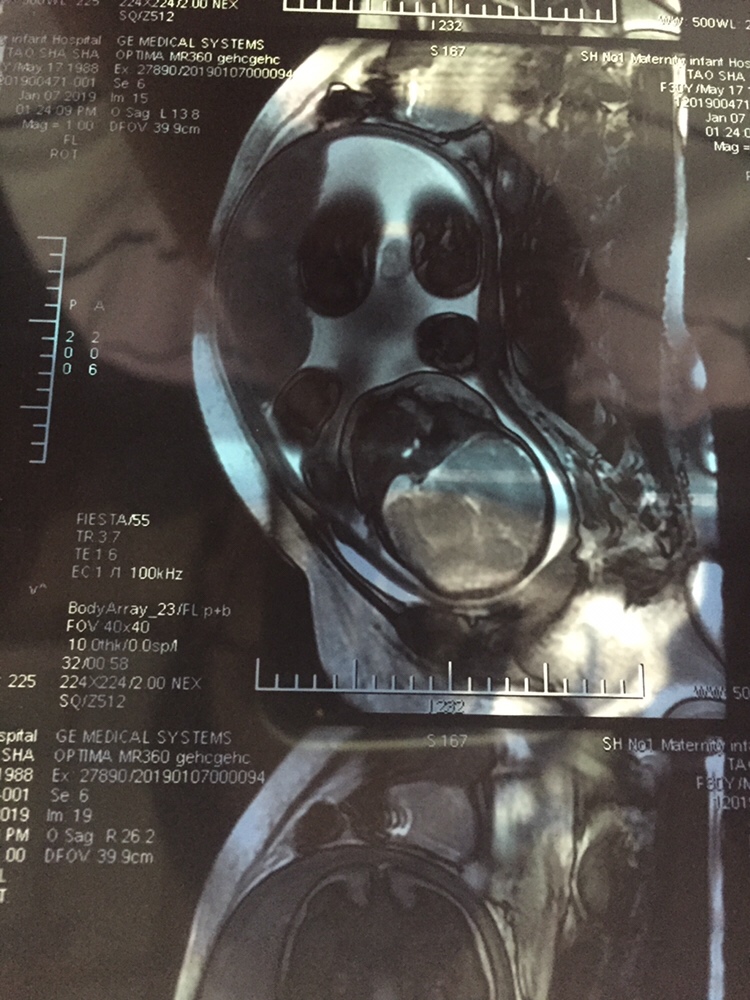

孕17周+0天

核磁共振对宝宝没有影响的吗

桃子[帖主]:没有辐射的,就是噪音非常大,胎动不安,很多孕妇做的

看了半天 没有看到孩子在哪里 哪里是头哪里是脚

团团思绮女王轻奢店(套现软件):下面是头

桃子[帖主]:为了排除胎盘植入的,不是必须做的

能拍核磁共振???

桃子[帖主]:排除胎盘植入的,因为有内膜炎和粘连,不是必须要做的

恭喜,是男宝宝吧

桃子[帖主]:好像是吧